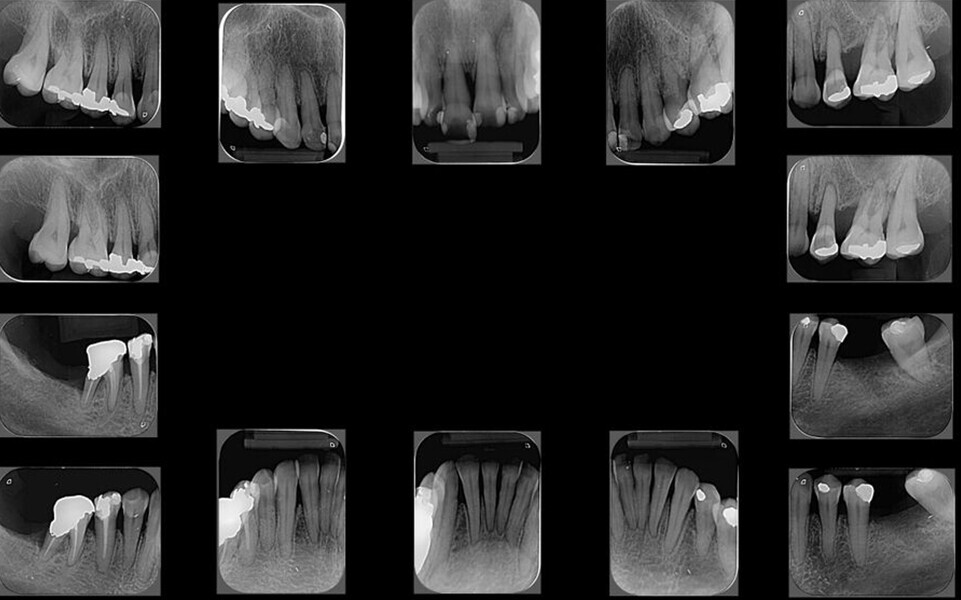

The periodontal treatment of an adult patient undergoing treatment with aligners is illustrated in demonstration of these points. Orthodontic planning considered the extra-oral photographs (Fig. 1) and intra-oral photographs (Figs. 2 & 3). Intra-oral scanning (Fig. 4) and radiographic documentation using panoramic radiographs and cephalometric radiographs (Figs. 5 & 6) were also carried out. From a periodontal perspective, periapical radiographs were recommended (Fig. 7), as this was an adult patient who smoked and showed clinical signs of advanced periodontal disease. Prior periodontal treatment was carried out (Fig. 8) to begin treatment with aligners (Fig. 9).